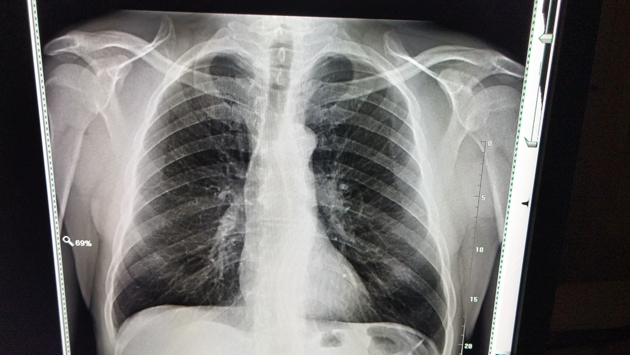

Рак легкого — один из самых смертельных в онкологии. Ежегодно он уносит более 1,8 миллиона жизней в мире. В России популярным методом диагностики рака легкого остается флюорография, которая входит в программу диспансеризации. Ежегодно ее проходят миллионы россиян, однако выявить опасное заболевание на ранней стадии с помощью флюорографии невозможно. Из-за поздней диагностики больше половины пациентов с таким диагнозом умирают в первый год после его постановки. Решить эту проблему может внедрение низкодозного КТ-скрининга, который уже доказал свою эффективность за рубежом, снизив смертность от рака легкого на 20 процентов. Как эта технология поможет спасти миллионы россиян, кому нужно проверяться в первую очередь и что делает старый метод диагностики фактически бессмысленным для защиты от одного из самых опасных видов рака, «Ленте.ру» рассказал директор Санкт-Петербургского НИИ фтизиопульмонологии, главный внештатный специалист Минздрава России по торакальной хирургии, профессор, заслуженный врач Петр Яблонский.

Была надежда, что массовая флюорография и диспансеризация помогут, однако эта надежда не оправдалась. Доказательные исследования показывают, что флюорография не подходит для ранней диагностики рака легкого и абсолютно непригодна в качестве скринингового метода. Скрининг — это метод, снижающий смертность. Именно поэтому мы сейчас выступаем за внедрение скрининга с помощью низкодозной компьютерной томографии (КТ), ее эффективность уже доказана.

К сожалению, да. Но это не означает, что больные с поздними стадиями неизлечимы. Сегодня есть химиотерапия, лучевая терапия, иммунотерапия, таргетная терапия — мы имеем возможность помогать. Но шансы на длительную выживаемость у больных с первой-второй стадией, конечно, выше. Поэтому мы ратуем за низкодозную КТ, которая помогает выявлять самые начальные формы опухоли, радикальное лечение которой — хирургическая операция — чаще всего дает надежду на выздоровление.